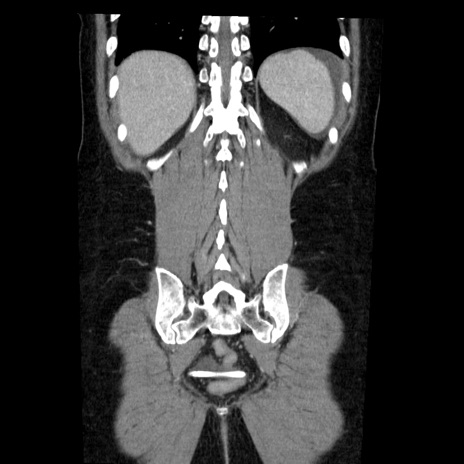

症例6(冠状断像)

【症例】50歳代女性

【主訴】下腹部痛

【現病歴】本日朝より下痢2回あり。 昼食を食べた後、嘔吐3回、下腹部痛認め、症状軽快せず、当院救急搬送。

最終食事:本日昼(生ものなし)。 昨日の夜、刺身を食ぺたとのこと。周囲に同様の症状の者なし。普段、排便は毎日あるとのこと。

【既往歴】卵巣癌術後(8年前に当院で卵巣摘出)

【身体所見】 意識清明、腹部:平坦、腸蠕動音→、やや硬、下腹部自発痛・圧痛あり、反跳痛あり、筋性防御なし。

【データ】WBC 16000、CRP 0.01